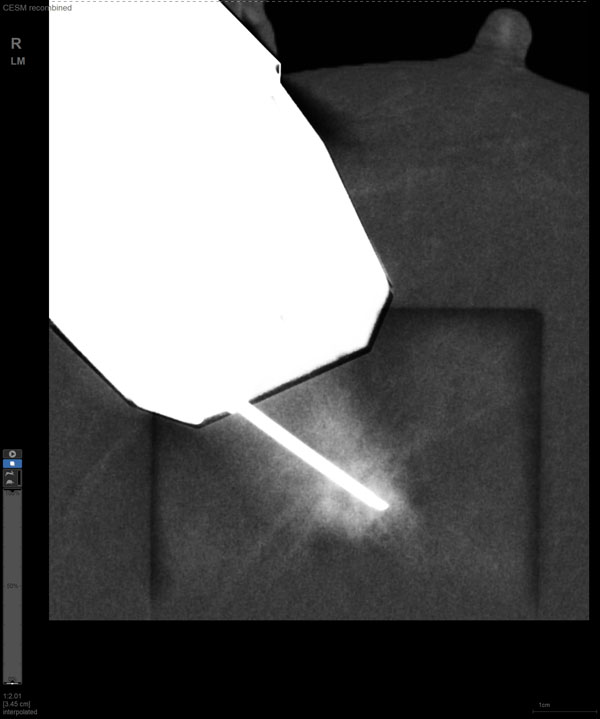

某患者增强磁共振成像MRI显示肿瘤周边有活性,中心区域有组织坏死。为得到准确的病理结果,穿刺靶区需避开肿物坏死区域。在与患者主管医生充分讨论后,放射科医生为患者行CEM引导下穿刺活检术。术中,CEM检查肿物同样显示为环形强化,巧妙避开坏死区域后,穿刺靶区选择了肿物增强早期明显强化区域,术程顺利,仅用时15分钟。术后该患者病理结果为浸润性导管癌Ⅱ级。

CEM作为近年来新兴的乳腺成像方法,是在传统乳腺X线摄影的基础上,通过静脉注射碘对比剂,用高低两种能量的X线摄影通过计算机进行能量减影处理,得到的减影像能突出显示病灶强化特征的一项新技术。其优势在于,既能显示乳腺病变的形态学特征,又能反映病变新生血管的血供情况,被越来越多地应用于临床。

随着计算机技术发展和乳腺X线机硬件的提升,CEM与立体定向活检技术相结合的CEM引导下穿刺活检术开始在临床应用。与MRI引导的乳腺穿刺活检相比,CEM穿刺活检无需抗核磁耗材,成本更低,检查速度更快。据国外研究文献报道,CEM引导的穿刺活检有可能成为MRI引导的乳腺穿刺活检的有效替代方案。